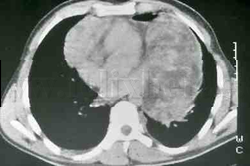

Teratoma |

Timoma |